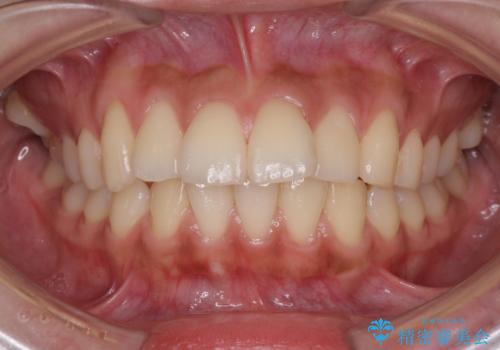

横顔をすっきりさせたい 下の前歯が1本少ない方の変則的な抜歯矯正

- 口元を引っ込めたいとのことで来院されました。

口元の突出感がありと、下顎の前歯が1本欠損していました。

上顎の前から両側の前から4番目の歯と、下あごの前歯を1本抜歯して、口元をすっきりさせる計画としました。